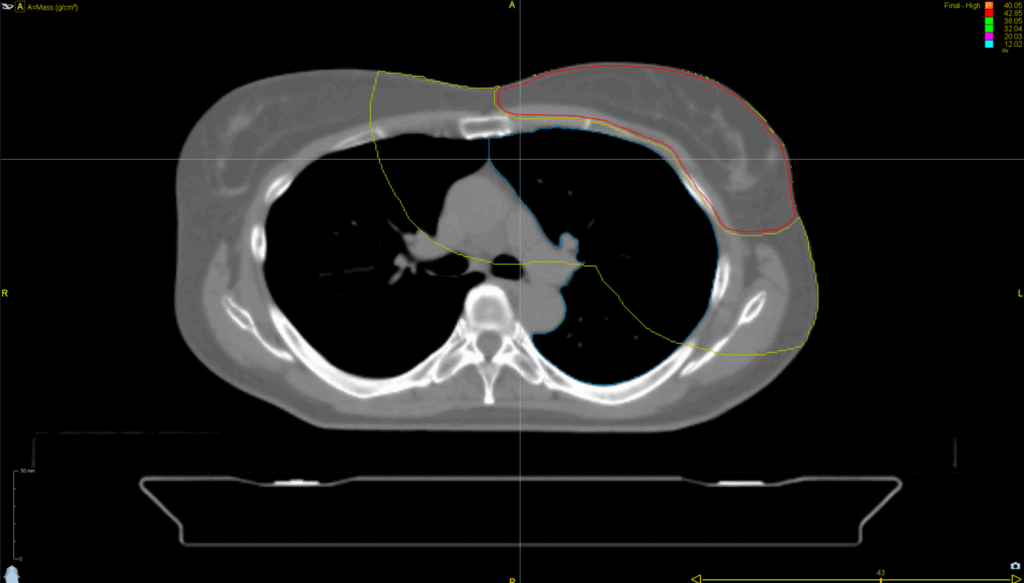

Left Breast with Deep Inspiration Breath Hold

< View All Plan Studies RADIXACT SYSTEM Left Breast with Deep Inspiration Breath Hold Case History AGE: 76-year-oldGENDER: Male Medical History Immidiate tolerance: Grade II dermatitis with eyelid edema, Grade I conjunctivitis resolved with Sterdex Diagnosis: Squamous cell carcinoma of the right lower eyelid Planning CT Images Treatment Plan Images ClearRT® Images Treatment Planning Highlights […]